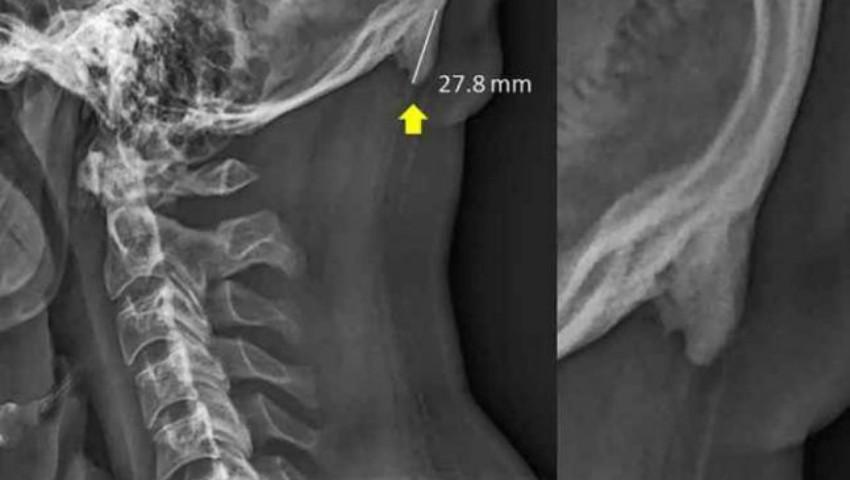

Studiul a fost realizat anul trecut, fiind din nou adus din nou în atenţia publicului, ca urmare a unui articol al celor de la BBC, care vorbeşte despre ”felul în care viaţa modernă transformă scheletul uman”.Tehnologia acţionează şi asupra scheletului uman, conform cercetătorilor.Ei au descoperit că aceste creşteri osoase sunt cauzate de înclinarea în faţă a capului, care mută greutatea de pe coloana vertebrală pe muşchii aflaţi pe partea din spate a capului, cauzând astfel o creştere a oaselor în ligamentele şi tendoanele conectate. Transferul de greutate în urma căruia apar aceste ”coarne” poate fi comparat cu felul în care pielea se îngroaşă şi se transformă într-o bătătură, ca răspuns la presiune sau abraziune.Unul dintre autorii studiului, chiropracticianul David Shahar, avertizează că această formaţiune constituie o deformare serioasă a posturii şi poate cauza dureri de cap şi dureri în partea superioară a spatelui şi în zona cefei, scrie adevarul.ro.El a fost surprins şi de mărimea pe care o ating aceste excrescenţe, majoritatea depăşind 10 milimetri, cu cea mai mare dintre ele atingând chiar 27,8 milimetri.Munca cercetătorilor a început cu trei ani în urmă, în Queensland, în urma unor scanări cu raze X ale zonei gâtului care au scos la iveală apariţia acestor ”coarne”, numite osteofite. Până atunci, prezenţa acestora era considerată a fi rară, însă Shahar a observat că ele se găseau în special pe scanările efectuate persoanelor tinere, deşi se credea că ele se formează doar la persoane în vârstă, datorită efortului şi presiunii continue asupra scheletului în timpul vieţii.”Aceste formaţiuni s-au dezvoltat într-o perioadă mai lungă, astfel încât cei care suferă de ele au aplicat probabil o presiune mare asupra zonei încă din copilărie” a explicat Shahar, citat de Washington Post.Faptul că această creştere a oaselor are loc pe o durată lungă de timp înseamnă şi că aceasta poate fi prevenită printr-o îmbunătăţire a posturii. Shahar sugerează că şcoala ar putea să îi înveţe pe copii reguli simple ale posturii, precum felul în care ar trebui să doarmă, pentru a anula efectele cauzate de folosirea telefonului mobil în timpul zilei.”Puteţi pune mâna pe zona respectivă din spatele capului, deasupra cefei. Cei care au aceste coarne le vor putea, cel mai probabil, simţi” a încheiat el.Până la apariţia unor examinări şi cercetări concludente pe această temă, este greu să realizăm o corelaţie definitivă între creşterea acestor coarne şi folosirea prelungită a telefonului mobil. Însă pericolul nu trebuie subestimat.